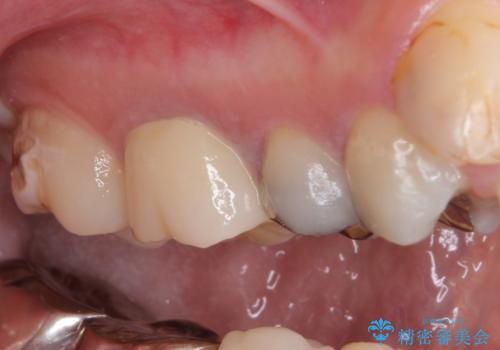

- 笑ったときに見てしまう上顎奥歯の銀歯を気にして来院された患者様です。

折角セラミッククラウンを装着するので、根管治療を行った後に補綴治療を行うこととしました。

他にも目立つ銀歯がありましたが、最も気にしている2本を優先して行うこととしました。

結婚式前にはクリーニングやホワイトニングを行い、その後他の歯を治療していく予定です。